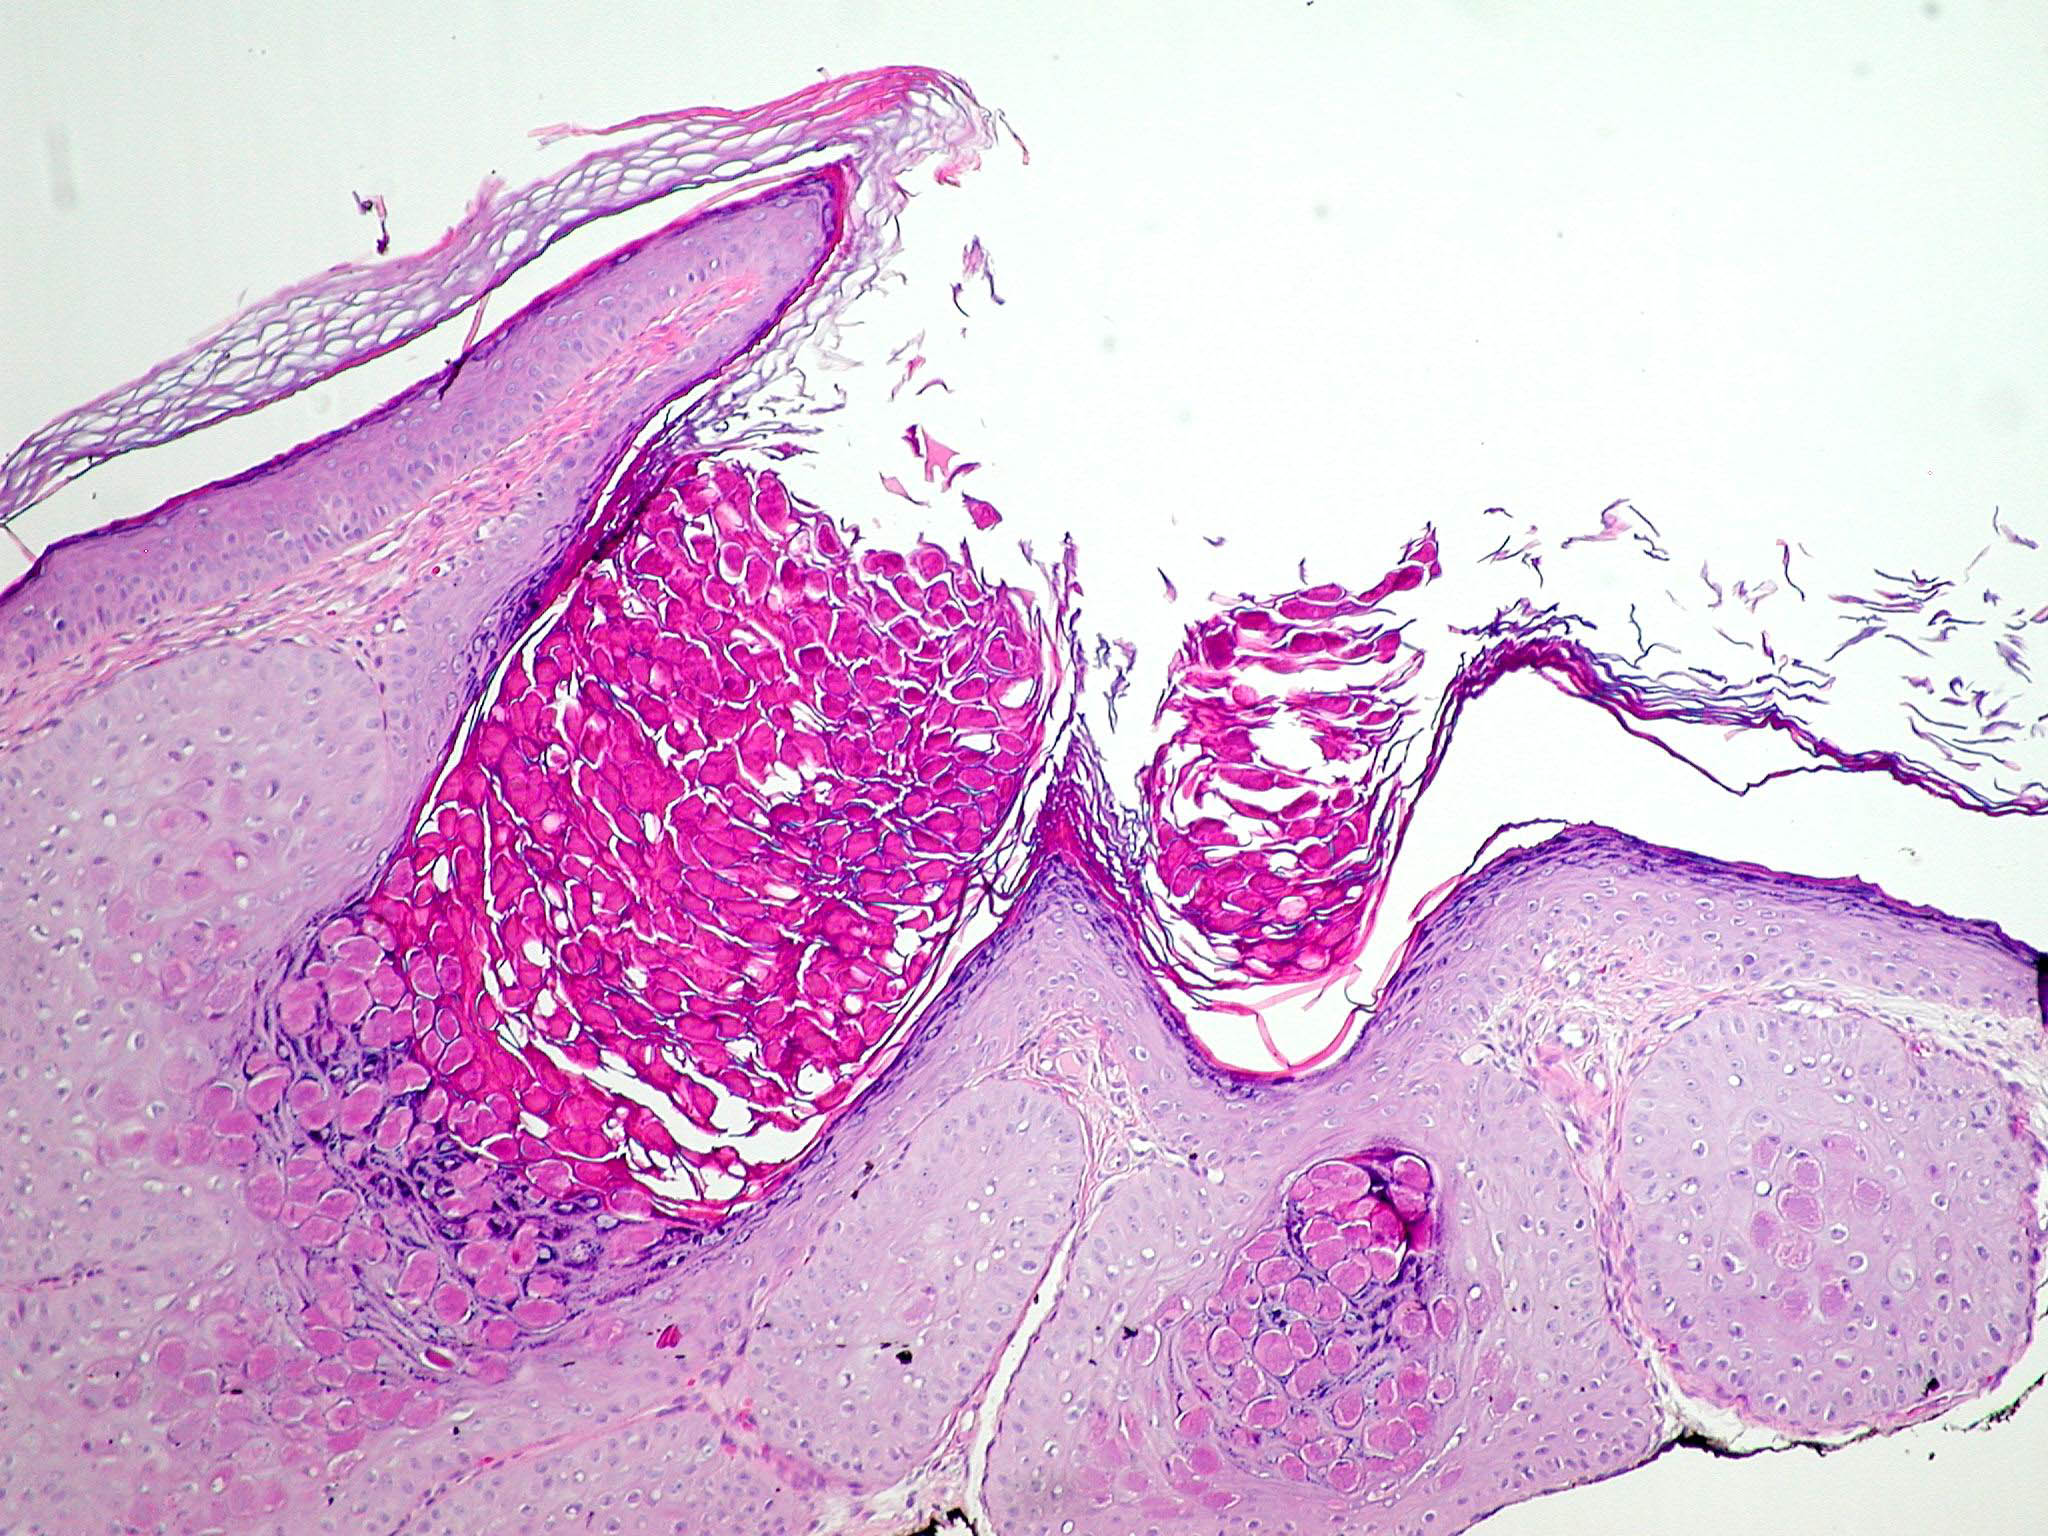

molluscum-contagiosum